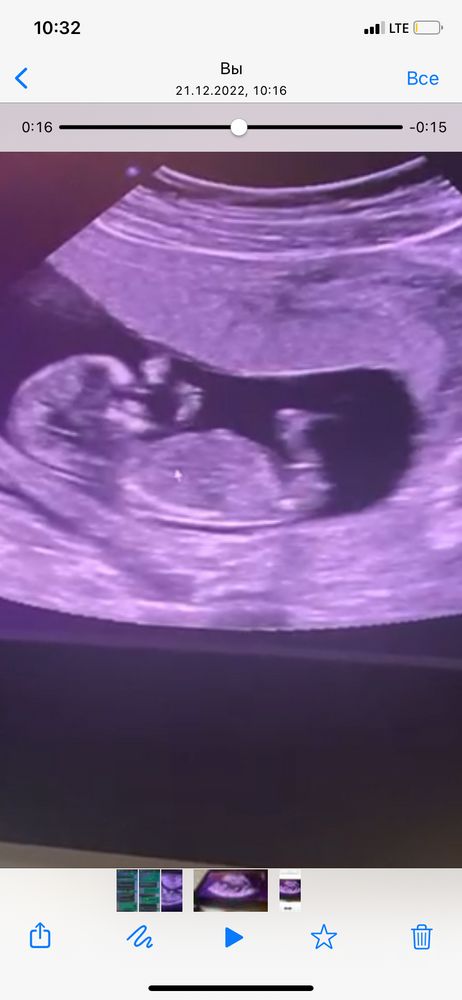

Ирина, ну лоб у нас у всех такой большой, у дочки тоже так было)) вот половой бугорок Изображение

Чем выше уровень разрешения аппарата УЗИ, тем точнее можно определить пол. Нам на первом скрининге сказали мальчик 90%, на втором показали писюн 😄